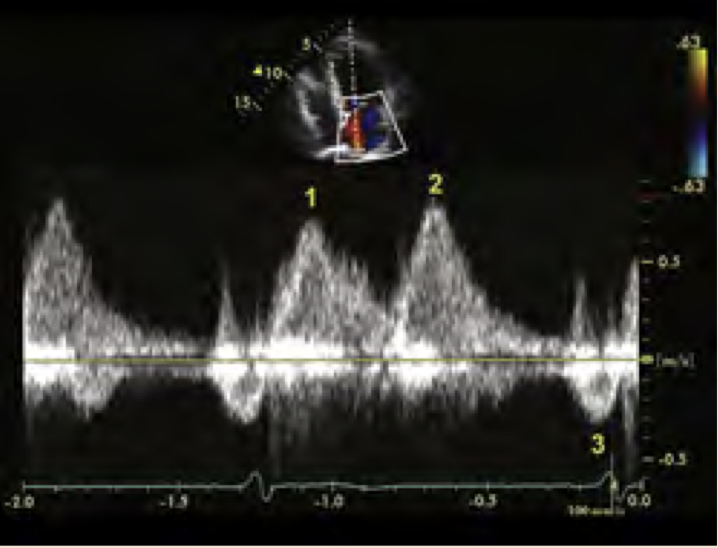

What waveform is this and is it PW or CW?

22